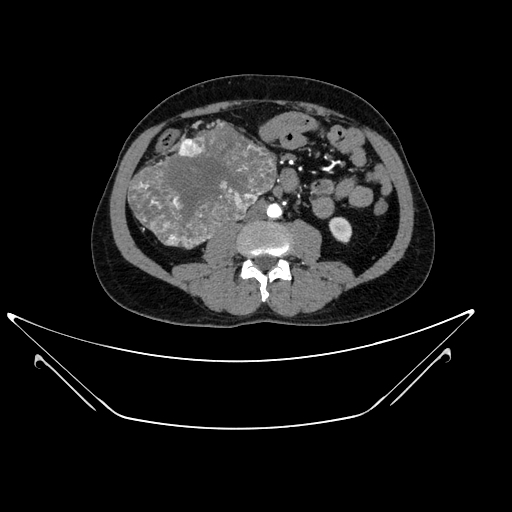

img

Stone